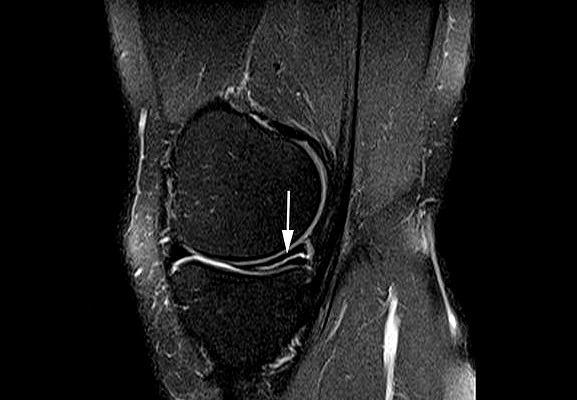

第一 , 增加患者经济负担 , 毕竟核磁检查费用是比较高的 , 频繁的、反复的进行核磁检查真的会增加有一些患者的负担 , 尤其是在一些经济欠发达的地区 。 本人所在的地区经济就是欠发达地区 , 建议患者做核磁非常的困难 , 更不要说术后反复的复查了 。 第二 , 核磁报告经常会提示“损伤信号”这样的结果 , 很多患者看到核磁报告单以后 , 会拿着报告单质问医生是不是手术没给做好 , 怎么做完了手术 , 核磁还显示有损伤信号 , 很容易发生医患之间的纠纷 , 有的时候 , 再解释也于事无补 , 因为患者已经认定了手术没有做好 。 那么为什么在复查的核磁结果上会有损伤信号呢 , 其实很简单 , 这就是由于手术本身也会造成半月板以及周边结构的水肿 , 在核磁影像上有些序列也是高亮的 。 而手术和真正的损伤在影像学上的的高亮信号并没有任何的区别 。 比如在下图的右侧箭头当中可以看到一些小的发亮的信号 , 这种情况往往在报告单上会被提示为:可见损伤信号 。 所以有些患者要求复查核磁时 , 本人会提前告诉患者 , 有可能会出现这种情况 , 打好预防针 , 患者就不会有太冲动的表现 。 其实 , 对于术后的患者来讲 , 在进行关节镜手术的时候 , 已经最直观的看到了患者的损伤 , 已经进行了处理 , 在术后的复查当中 , 主要还是要依靠医生的查体以及患者的症状 , 如果没有特殊的症状 , 也没有特殊的查体表现 , 其实没有必要复查核磁 。

很多朋友会问为什么术后几个月复查核磁 , 还显示有这些高亮损伤的信号呢 , 其实这也是由于半月板的结构来决定的 , 半月板这种结构它缺少血供 , 所以一旦发生损伤 , 恢复的能力特别弱 , 在术后3~6个月内仍然有一些异常的信号 , 就是由于血液循环差 , 吸收不是特别好 , 极其缓慢导致的 。